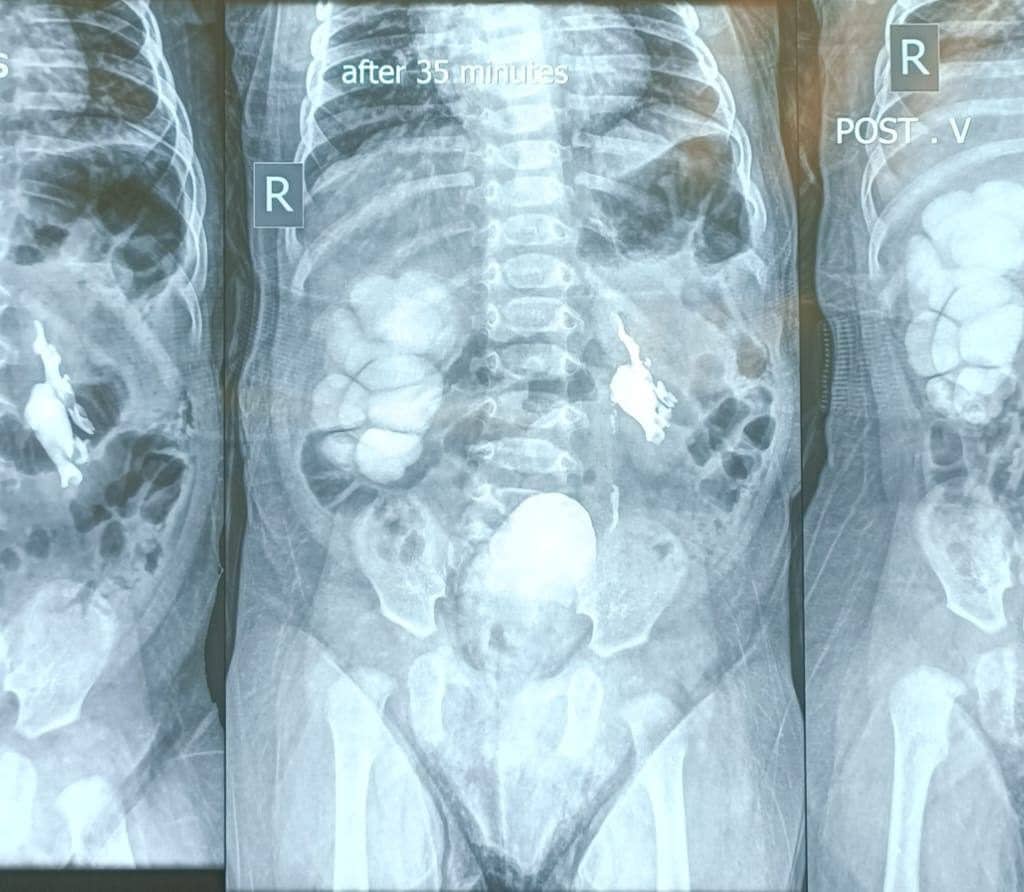

“أجرينا بفضل الله تعالى عمليات ناجحة لتصحيح تشوهات خلقية لدى ثلاثة أطفال كانوا يعانون من انسداد في كلا الحالبين، ما أدى إلى توسع في الكليتين وتسبب بحالة من عدم الارتياح والبكاء المستمر.”

“تراوحت أعمار الأطفال بين ستة أشهر وسنة وشهرين، وقد تزامن أن كل طفل منهم كان يعاني من درجتين مختلفتين من الانسداد؛ انسداد متوسط في أحد الحالبين، وانسداد شديد في الحالب الآخر.”

“تم التعامل مع الانسداد الشديد من خلال إجراء عملية تجميل حوض الكلية لإعادة تصحيح مسار البول، فيما عولج الانسداد المتوسط بواسطة الفتح الناظوري للحالب، وهو إجراء دقيق يساعد على إعادة انسيابية جريان البول.”

“الحمد لله، تكللت العمليات بالنجاح، وتمت استعادة عمل الجهاز البولي بصورة طبيعية، وغادر الأطفال المستشفى وهم في أتم الصحة والعافية.”